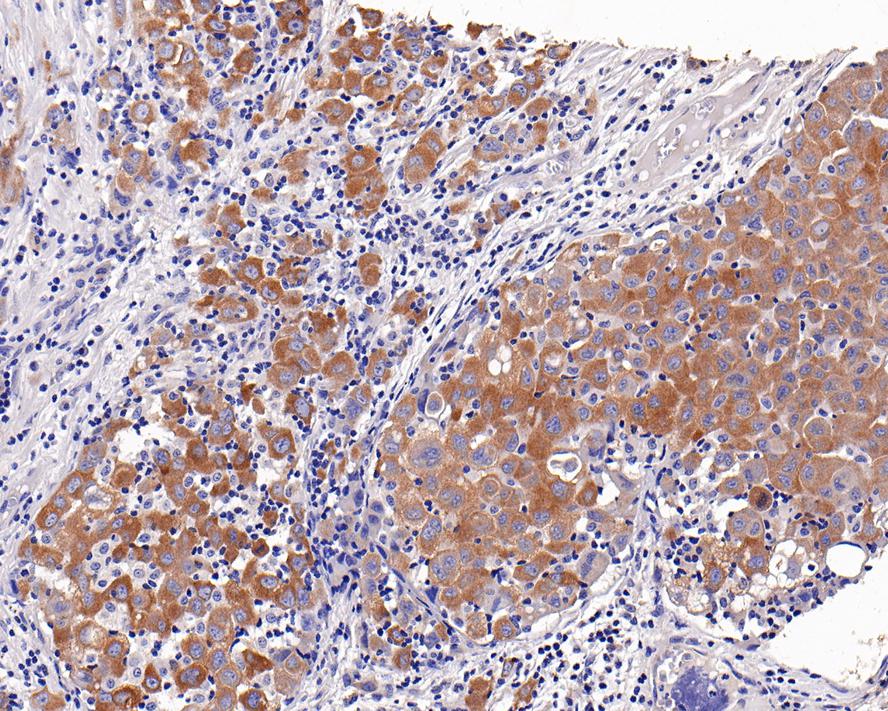

c-Met Mouse Monoclonal Antibody [A9A5]

IHC-P

Human